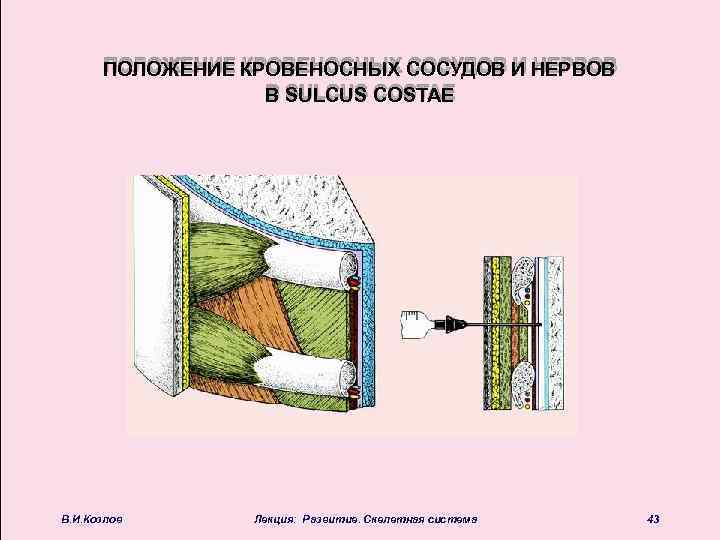

ПОЛОЖЕНИЕ КРОВЕНОСНЫХ СОСУДОВ И НЕРВОВ В SULCUS COSTAE В. И. Козлов Лекция: Развитие. Скелетная система 43